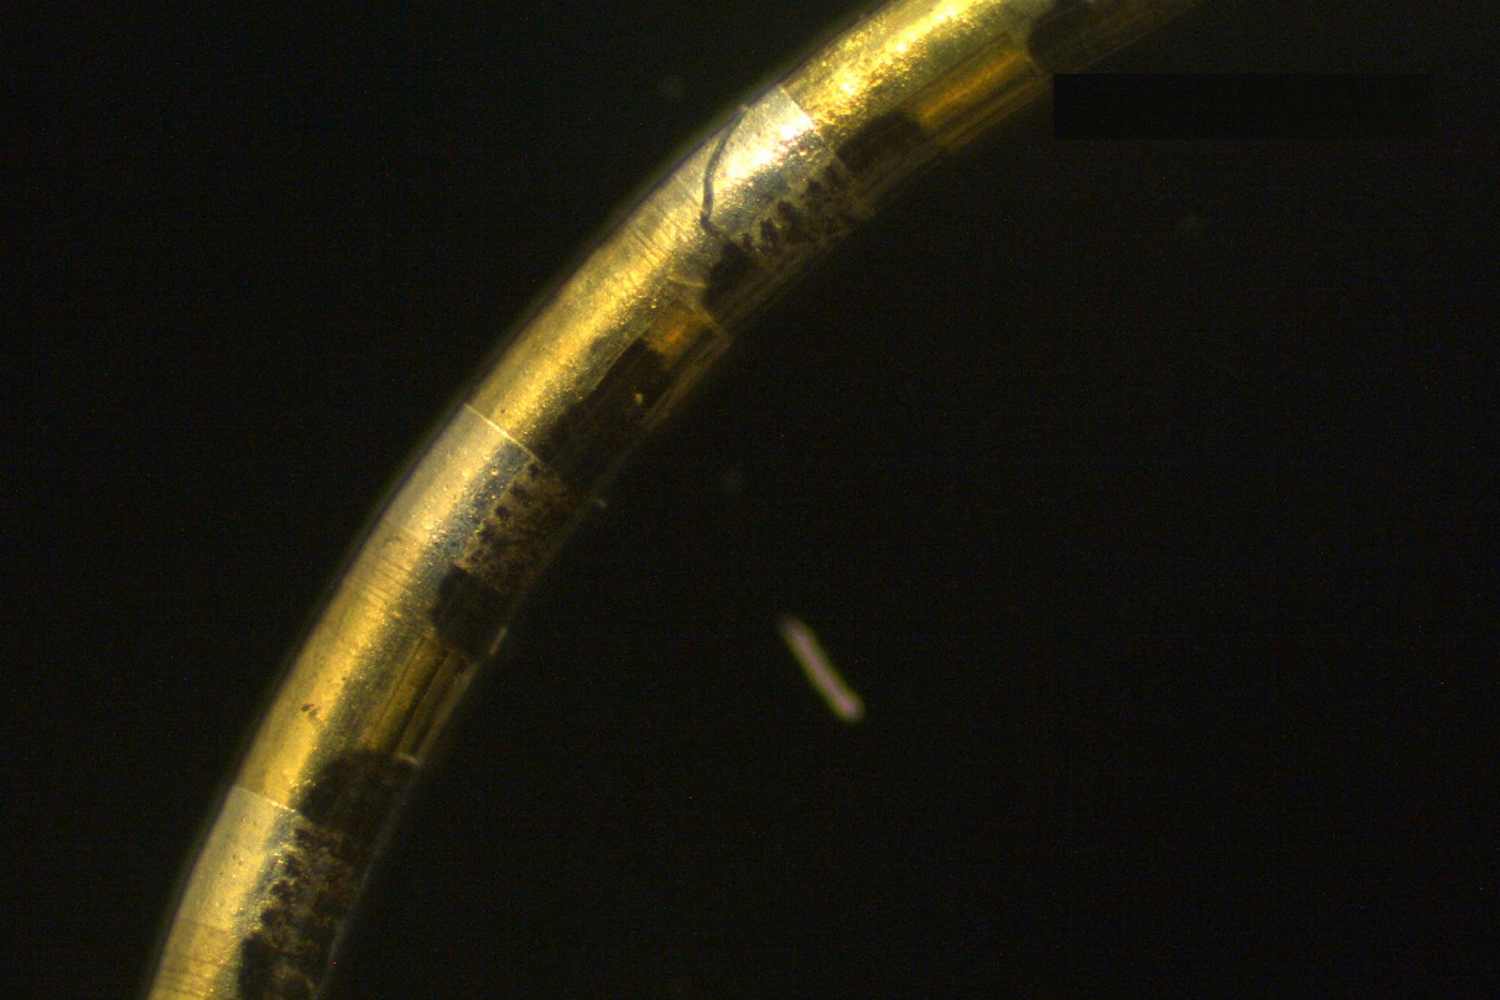

Stanford researchers have developed a remarkable new technology called Spiral-NeuroString (S-NeuroString), a soft electronic fiber about the width of a human hair that can monitor and stimulate tissues in the body. This tiny fiber, measuring just a quarter of a millimeter (230 micrometers) in diameter, can pack up to 1,280 electronic channels within its slim profile.

What makes S-NeuroString special is its innovative “spiral transformation” manufacturing process. Researchers first create a flat, thin film with electronic components using standard microfabrication methods.

Then, they roll this film tightly like a Swiss roll, with sensors exposed on the surface while connecting wires spiral inside. This approach allows precise control of component placement and enables the high density of electronic channels.